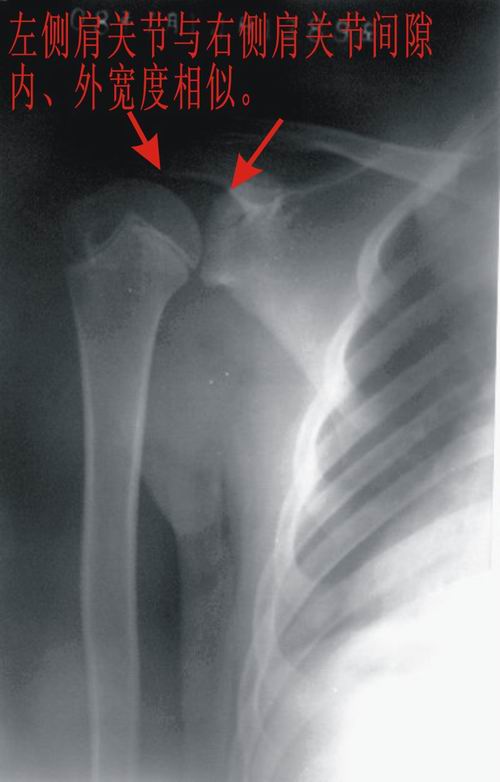

患者,男,13岁。自诉两月前双肩关节时有弹响,有时左、右肩关节轮换隐痛。但双上肢能抬举、左右旋转、屈伸自如。pe:双肩及双上肢皮肤无红、肿。触诊:双肩关节区域有抖动,似触心脏的搏动感,但抖动、搏动感能自控。双肩区域皮肤无发热。听诊:用耳贴近患者双肩区能听到弹响声。x线胸部后前位示:双肩关节间隙增宽,考虑双肩关节半脱位。双肩关节正侧位片示:双肩关节无明显脱位征象。双肩关节区域透视示:双肩关节解剖位时,双肩关节间隙增宽(与胸部后前位的双肩关节间隙相等),也能见双肱骨头在双肩关节腔内上、下移动约1cm左、右。但患者能自控(双肱骨头在双肩关节腔内不上、下移动)。请战友们详见患者相片、胸部后前位片、双肩关节正侧位片。我第一次碰到这样的病例(是否是神经性关节病“夏科氏关节”?),经验不足,希望能帮助诊断。亦请分析病因、病理机制,是什么原造成的?最好能提供治疗方法,谢谢!

双侧肩关节解剖位时,双肩关节间隙增宽,但肱骨头及周边骨质 关节腔均未见异常。与骨科专家会诊结果,目前只能诊断:肩关节松弛症!

双肩关节间隙增宽,但肱骨头及周边骨质 关节腔均未见异常。